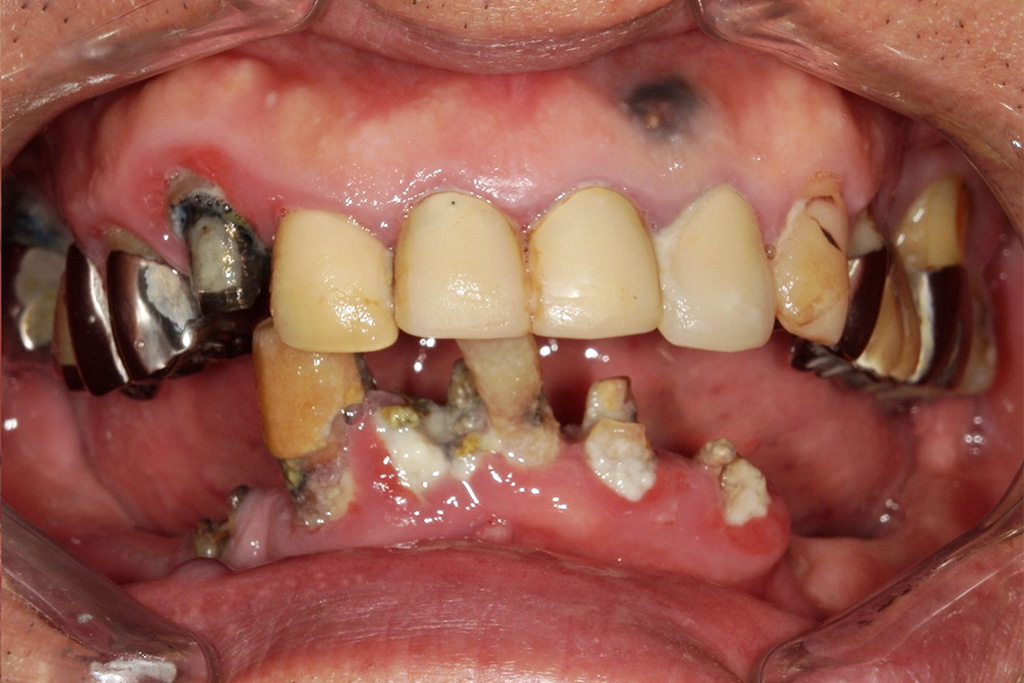

Hさまは今まで歯医者が嫌いで行かないでそのまま放置していました。タバコもヘビースモーカーと自分で言うくらいの量を吸っていたそうです。

放置していたらどんどん歯がボロボロになっていき、噛めないことと痛みがあるのでどうしたらいいかと、重い腰を上げてきてくださいました。

今回は噛めることと見た目の改善を目的として上顎はダメな部分は抜歯をし、インプラントを入れました。

Hさまのインプラント治療は1年かかりました。理由としてはヘビースモーカーのためインプラントが骨と定着しなかった部分があったため何本か抜けてしまったりし、再度インプラントを入れ直したり等したためです。

タバコを止めることがストレスになるとのことでした。インプラント治療には禁煙は必須ですがストレスのが強いのであれば、インプラントが定着せず抜けてしまう可能性は増えますが、辛抱強く行えばインプラントはいつかは定着すると私も勉強させられました。

ヘビースモーカーでも治療が可能と今では言える様になりました。(歯科医師としては言ってはいけないと思いますが・・・)

現在では硬いものもかめてやってよかったと言われて私は満足しかありません。

かなりボロボロでもこのような難症例であろうと私は治療ができると自信がつきました。